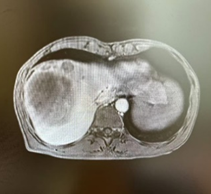

新辅助治疗前CT

由于病人一般情况较好,肝功能良好(Child-pugh A级),经多学科会诊临床确认肿瘤为IIb期肝细胞癌,属于可切除性肝癌,但存在高危复发因素,建议先行新辅助治疗后手术切除。经两次肝动脉关注化疗(HAIC)(奥沙利铂+5-Fu+亚叶酸钙方案)和两个周期的靶向免疫治疗(仑伐替尼+帕博利珠单抗方案),第二次介入造影是肿瘤血供不明显,第二次介入治疗4周后复查CT提示肿瘤缩小不明显但坏死征象明显,经MRI证实仍有少许血供,于是经多学科会诊后决定行前入路右半肝切除术。